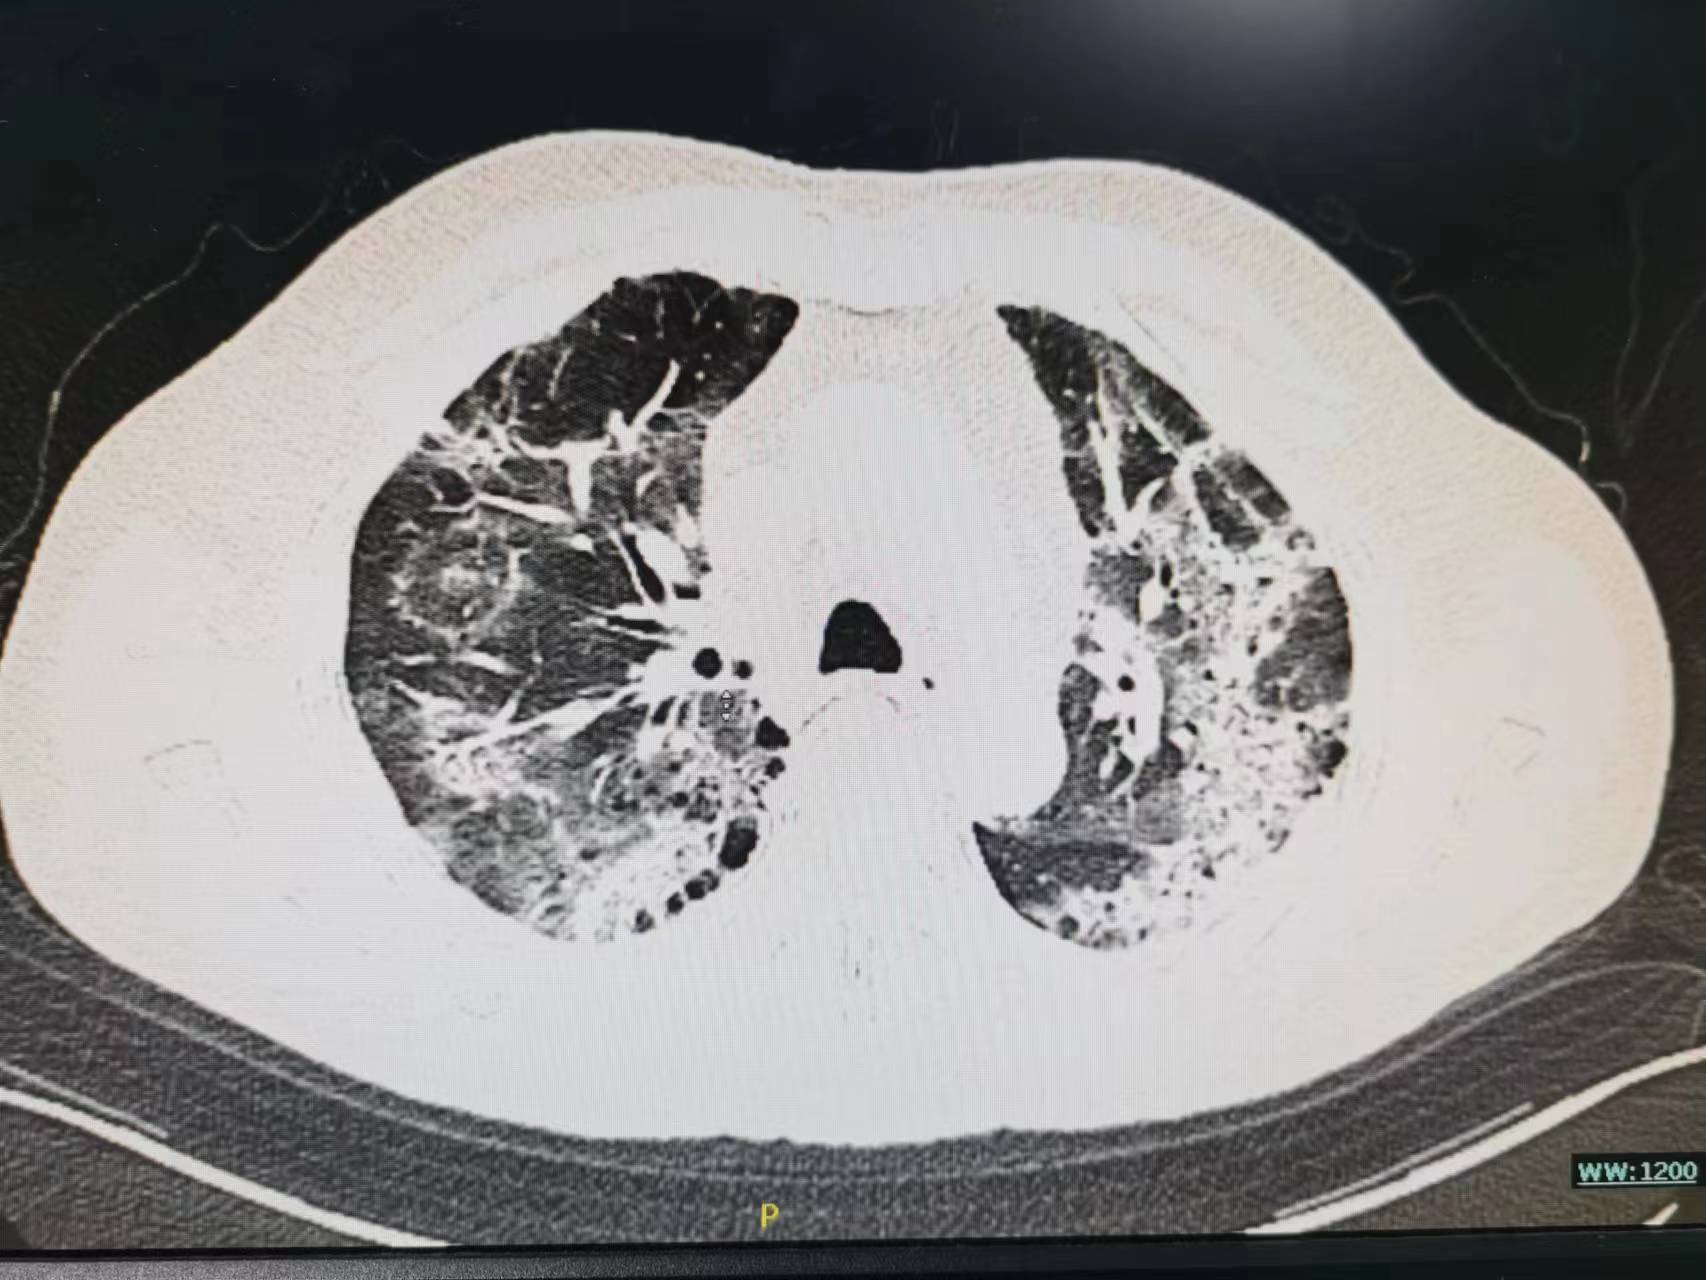

开始家属接受不了,找关系送老太太来医院是为了打“点滴”的,你给我说这个合适吗?病人的情况真有这么重吗?现在老太太不是好好的吗?于是再次向家属讲解病情,重点讲述了病人病情可能的发展并告知可能需要呼吸机,家属还是觉的不可能,查了胸部CT之后才发现病情已如此严重了,基本白肺了。这时候老太太才说这几天感觉到有点“憋的慌”,只是限于不想麻烦孩子的关系不想说,觉的忍忍就过去了。最后还是拗不过家属的要求才来医院的。

老年人阳后长期低热,肺部感染